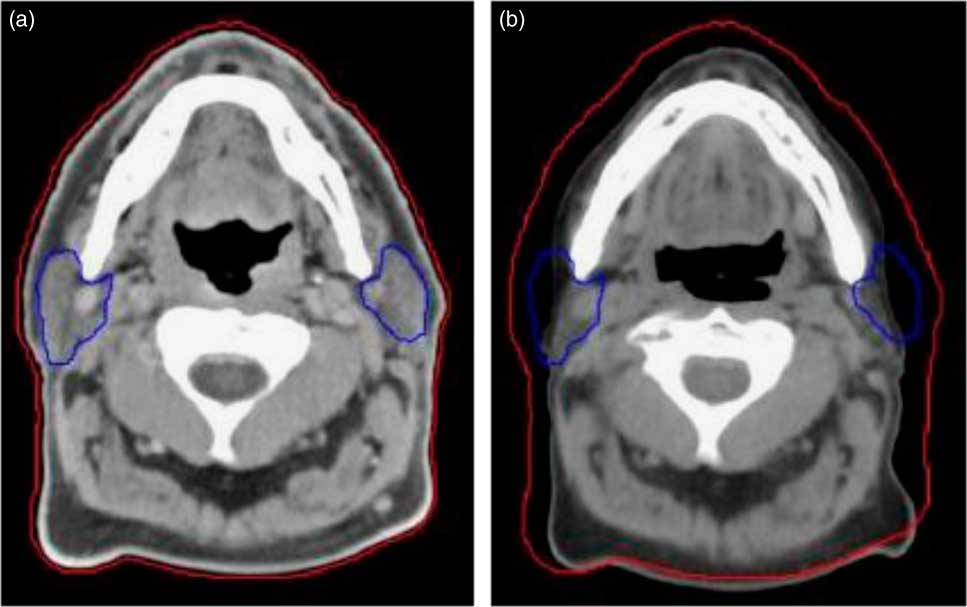

1. Patients who were likely to have tumour shrinkage due to response and weight loss at 20th fraction (usually in head and neck patients the weight loss or tumour shrinkage occurs in 4th week of the treatment fraction) in the course of radiotherapyReference Wang, Yang and Hu 8 (Figure 1).

Figure 1 Compared to the planning CT (a), a rescan at 20th fraction (mid-way) through treatment (b) highlights weight loss and changes to the parotids. The external contour is shown by the red line and the parotids by the blue line.